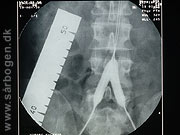

Før PTA af iliacakar...

Zoom

Under PTA af iliacak...

Efter PTA af iliacak...